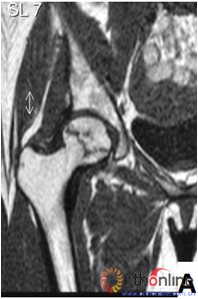

图3 各型坏死打压植骨的结果,(A)Ⅰ型(右侧)和Ⅱ型(左侧)术前MRI显示外侧柱存留;(B)术后7年随访,股骨头维持外形,关节功能好;(C)Ⅲ型(双侧)术前MRI显示外侧柱破坏;(D)术后5年,右侧股骨头维持外形,左侧塌陷

Fig 3 The results of different osteonecrotic type by impacting bone graft,(A)Type Ⅰ(right),type Ⅱ(left) MRI showed the preservation of the lateral pillar preoperatively; (B) Seven years after operation, the femoral head still maintain sphere, hip function is excellent; (C) Type Ⅲ (both side) MRI showed the involved of lateral pillar by necrosis; (D)Five years after operation, the femoral head still maintain sphere in right side, collapse occurred in left side.